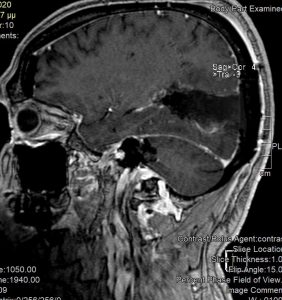

Ασθενής άνδρας, 65 ετών ο οποίος παρουσίασε αρχικά αίσθημα κόπωσης και διαλείπουσες κεφαλαλγίες. Ο νευροαπεικονιστικός έλεγχος με μαγνητική τομογραφία με σκιαγραφικό ανέδειξε χωροκατακτητική εξεργασία στην περιοχή του αριστερού σφηνοειδούς λοβίου με επέκταση και υποεπενδυματική διήθηση του ινιακού κέρατος.

Η μετεγχειρητική μαγνητική τομογραφία εγκεφάλου )βλ. εικόνα) εντός 48ωρου επιβεβαιώνει την ολική εξαίρεση του όγκου.